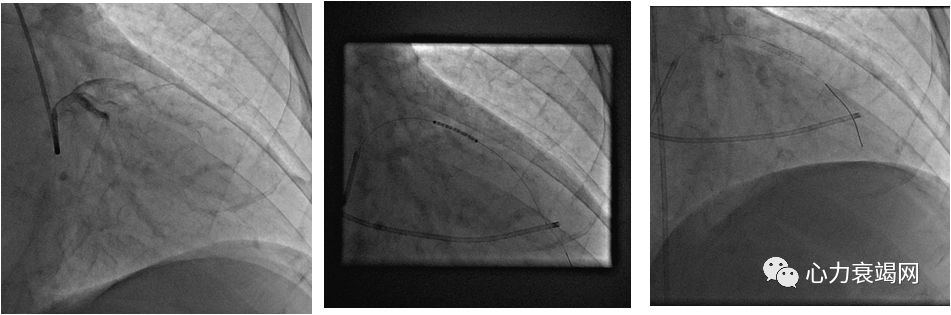

经皮腔内间隔心肌消融术

(PTSMA)

PTSMA由英国医生Sigwart于1991年首次应用于治疗HOCM并取得良好的疗效,随着经验的积累和方法学上的不断改进,该方法日趋成熟,逐渐成为HOCM的主要治疗手段之一

是介入手段,通过导管注入无水酒精,闭塞冠状动脉的间隔支,使其支配的肥厚室间隔心肌缺血、坏死、变薄、收缩力下降,是流出道梗阻消失或减轻。从而改善HOCM患者的临床症状

我科2004-至今,32例PTSMA的病例

特殊病例的HOCM-PTSMA术(case 1)

特殊病例的HOCM-PTSMA术(case 2)